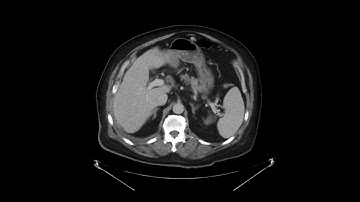

AUTOMATIC SEGMENTATION OF PANCREAS AND PANCREATIC TUMOR USING DEEP LEARNING